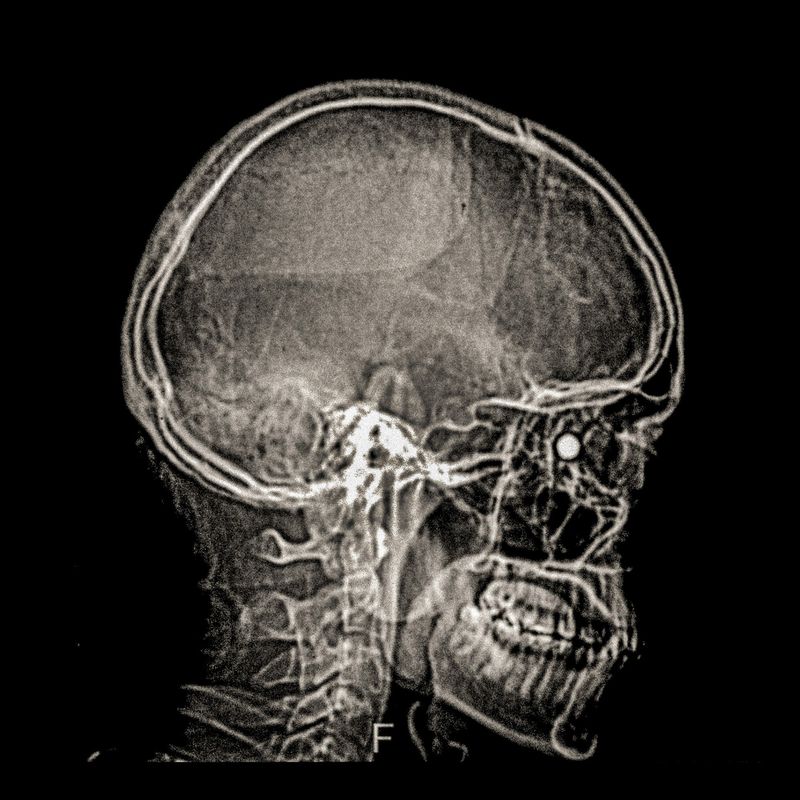

X ray showing the embedded pellet of an injured man during Santiago protests.